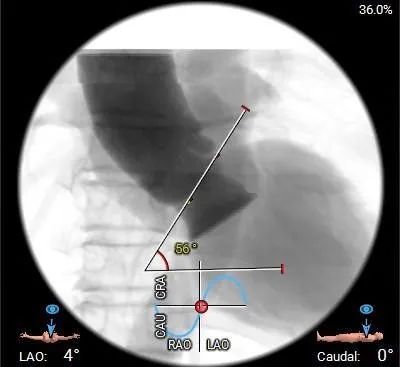

水平夹角测量

虚拟瓣环与水平面夹角56°,非横位心